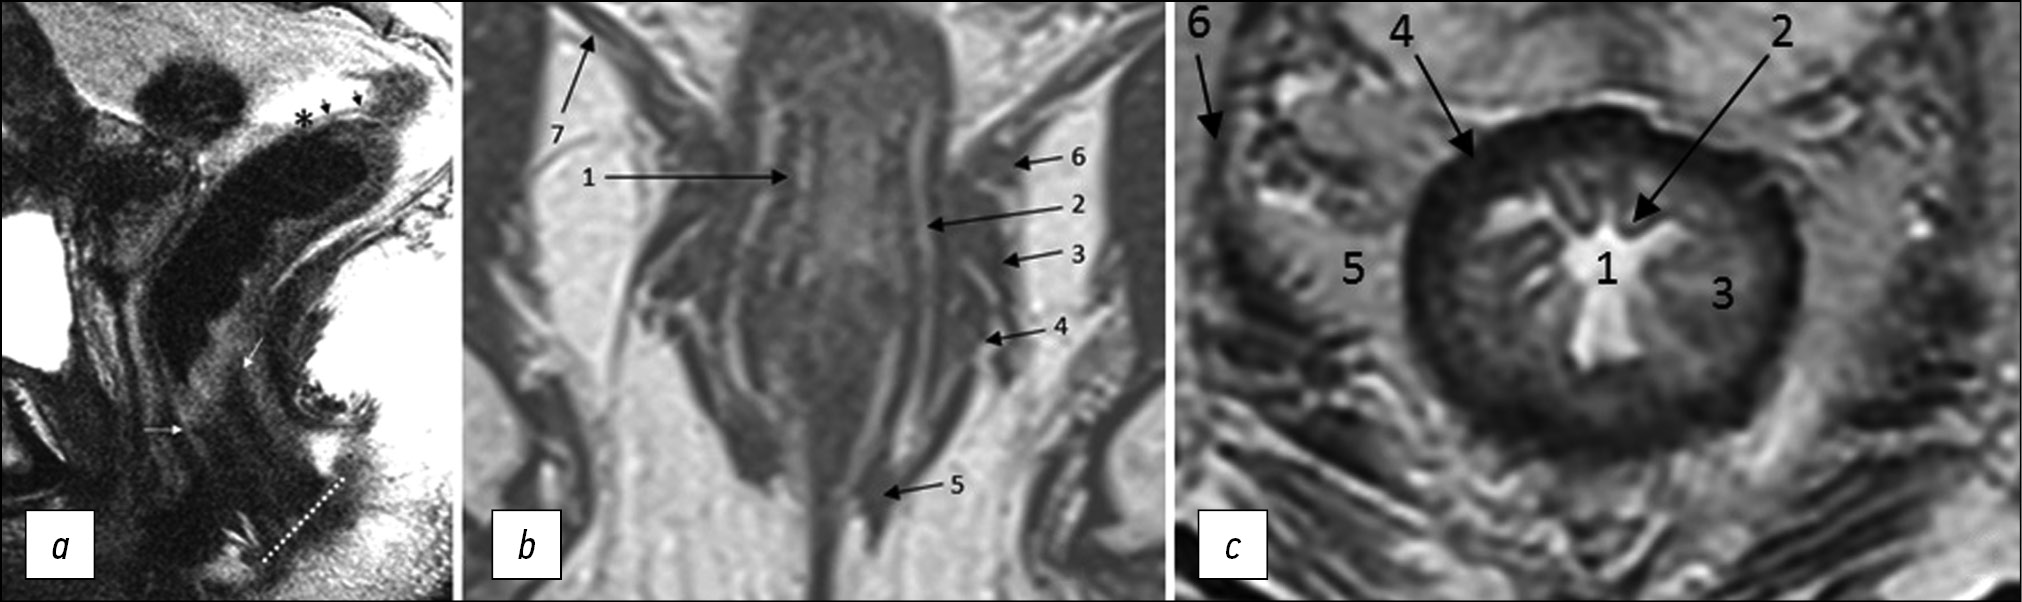

The anal margin refers to the anocutaneous line, the junction of the anoderm with the perianal skin, corresponding to the distal edge of the internal sphincter of the anal canal/intersphincteric groove on sagittal MRI (Fig. 1). From this level, the distance to the lower edge of the tumor is measured on sagittal T2-weighted images along the center of the lumen of the anal canal and rectum [6].

The anorectal junction is the connection between the anal canal and the rectum, corresponding to the upper edge of the puborectalis muscle, clearly defined on T2-WI in the coronal plane, or the anorectal angle, defined on T2-WI in the sagittal plane (Fig. 1). The distance from the anorectal junction to the inferior margin of the tumor is important for surgery planning and should be indicated in the diagnostic report [6].

The anal sphincter complex includes the internal and external anal sphincters and the puborectalis muscle (Fig. 1).

Fig. 1. MRI anatomy of the rectum on T2-WI. (a) Sagittal plane: anal edge (intersphincteric groove; dotted line); anorectal junction (angle) at the level of the upper border of the internal sphincter of the anal canal (white arrows); transitional fold of the peritoneum at the lower point of attachment of the pelvic visceral peritoneum to the rectal wall (asterisk); peritonealized part of the rectum (black arrows). (b) Coronal plane: 1, internal sphincter of the anal canal; 2, intersphincteric space; 3, deep portion of the external sphincter; 4, superficial portion of the external sphincter; 5, subcutaneous portion of the external sphincter; 6, puborectalis muscle; 7, elevator muscle of anus (levator ani). (c) Axial plane: 1, intestinal lumen; 2, mucous membrane; 3, submucosal layer; 4, muscle layer; 5, mesorectal tissue; 6 mesorectal fascia.

The internal anal sphincter is a continuation of the internal circular muscle layer of the rectum, comprising smooth muscle tissue. On MRI, it is determined by a significant thickening of the intrinsic muscle layer of the wall at the level of the anal canal (Fig. 1). The signal from the internal sphincter on T2-weighted images is slightly higher than that of the external sphincter, and with contrast enhancement, it appears more intense.

The external anal sphincter is a striated muscle, which is a continuation of the puborectal muscle, divided into three layers, such as the subcutaneous circular layer, superficial ellipsoidal layer, connected to the coccyx, and deep layer, closely connected with the puborectalis muscle (Fig. 1).

The intersphincteric space is a connective-cellular tissue space that separates internal and external anal sphincters and is characterized by a high signal on T2-WI (Fig. 1).

Mesorectal fascia is a thin fascial sheath that limits the rectum and the surrounding fatty tissue. On T2-WI, it appears as a hypointense circular line (Fig. 1). In men, the mesorectal fascia in front merges with the Denonvilliers’ fascia, while in women, it merges with the rectovaginal fascia (septum). At the back, it connects with the presacral fascia; it completely surrounds the rectum only to the level of the transitional fold of the peritoneum with its lateral and posterior parts above and only the posterior rectum at the level of the upper ampullary. Caudally, the mesorectal fascia passes into the intersphincteric space.

The muscular layer of the rectum consists of an inner circular and outer longitudinal layer, which are defined as a single hypointense layer on T2-weighted MRI images, limited internally by a hyperintense submucosal layer and externally by hyperintense mesorectal tissue (Fig. 1).

The elevator muscle of the anus (m. levator ani) is a muscle complex (Fig. 1), consisting of the puborectalis, pubococcygeus, iliococcygeus, and anal-coccygeal fibrous muscles and anococcygeal ligament. Tumors infiltrating the elevator muscle of anus are classified as T4b.

The transitional fold of peritoneum is formed at the point of transition of the peritoneum from the pelvic organs to the rectal wall, with the lower point of attachment along the anterior wall of the intestine and obliquely going up the side walls. It separates the peritonized and non-peritonized parts of the rectum. On T2-WI, it appears as a hypointense line, displaying a V-shape in the axial plane, and passes from the apex of the seminal vesicles (in men) or from the body of the uterus (in women) in the sagittal plane (Fig. 1). Lymphatic drainage from tumors located above the transitional fold of the peritoneum mainly occurs through the upper rectal and lower mesenteric lymph nodes. Tumors below the transitional fold of the peritoneum can drain through the internal iliac and obturator lymph nodes. When describing MRI findings, it is recommended to indicate the position of the tumor relative to the transitional fold of the peritoneum (completely below/crosses/completely above) [6].